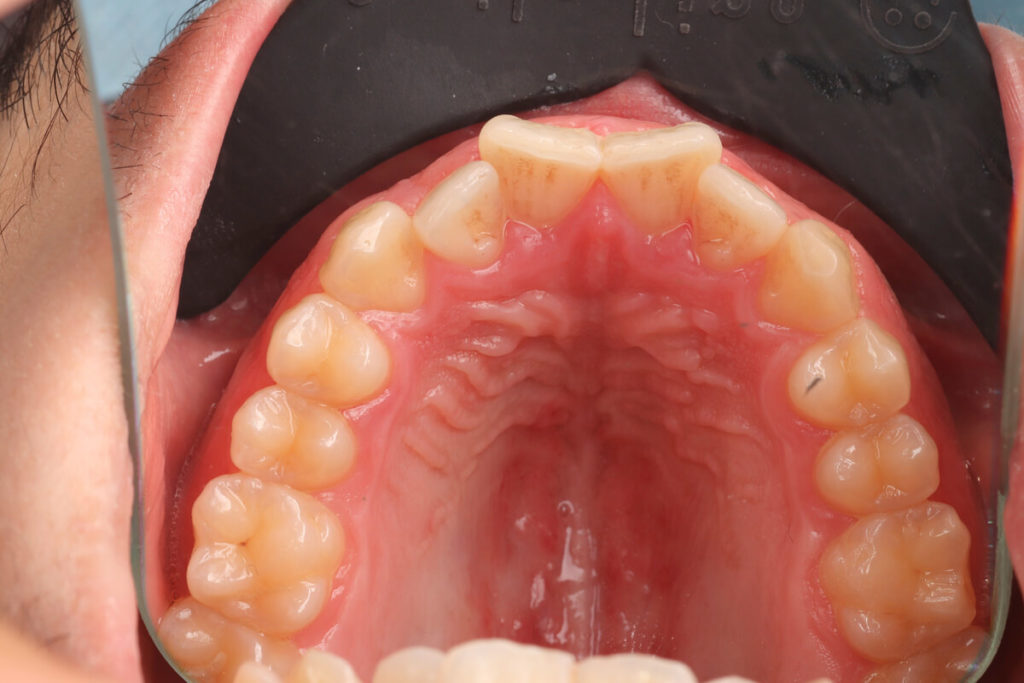

SITUACIÓN INICIAL

CLASE I MORDIDA CRUZADA EN LATERALES

• Clase I con mordida cruzada en los incisivos laterales.

• Apiñamiento moderado en el arco superior e inferior.

• Desplazamiento de la línea media superior.

• Arco normal con necesidad de expansión.